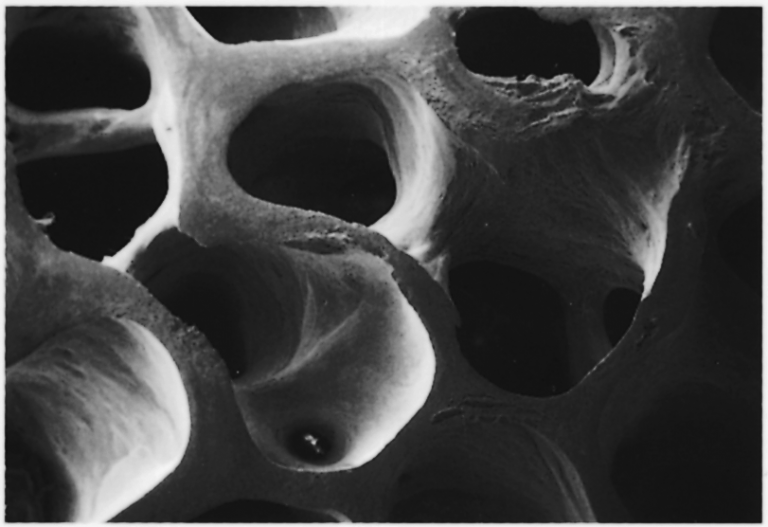

Op de afbeeldingen hieronder ziet u grote gelijkenis tussen de structuur van het natuurlijke kunstbot Geistlich Bio-Oss® en uw eigen bot.

Geistlich Bio-Oss®

Menselijk bot (humaan)